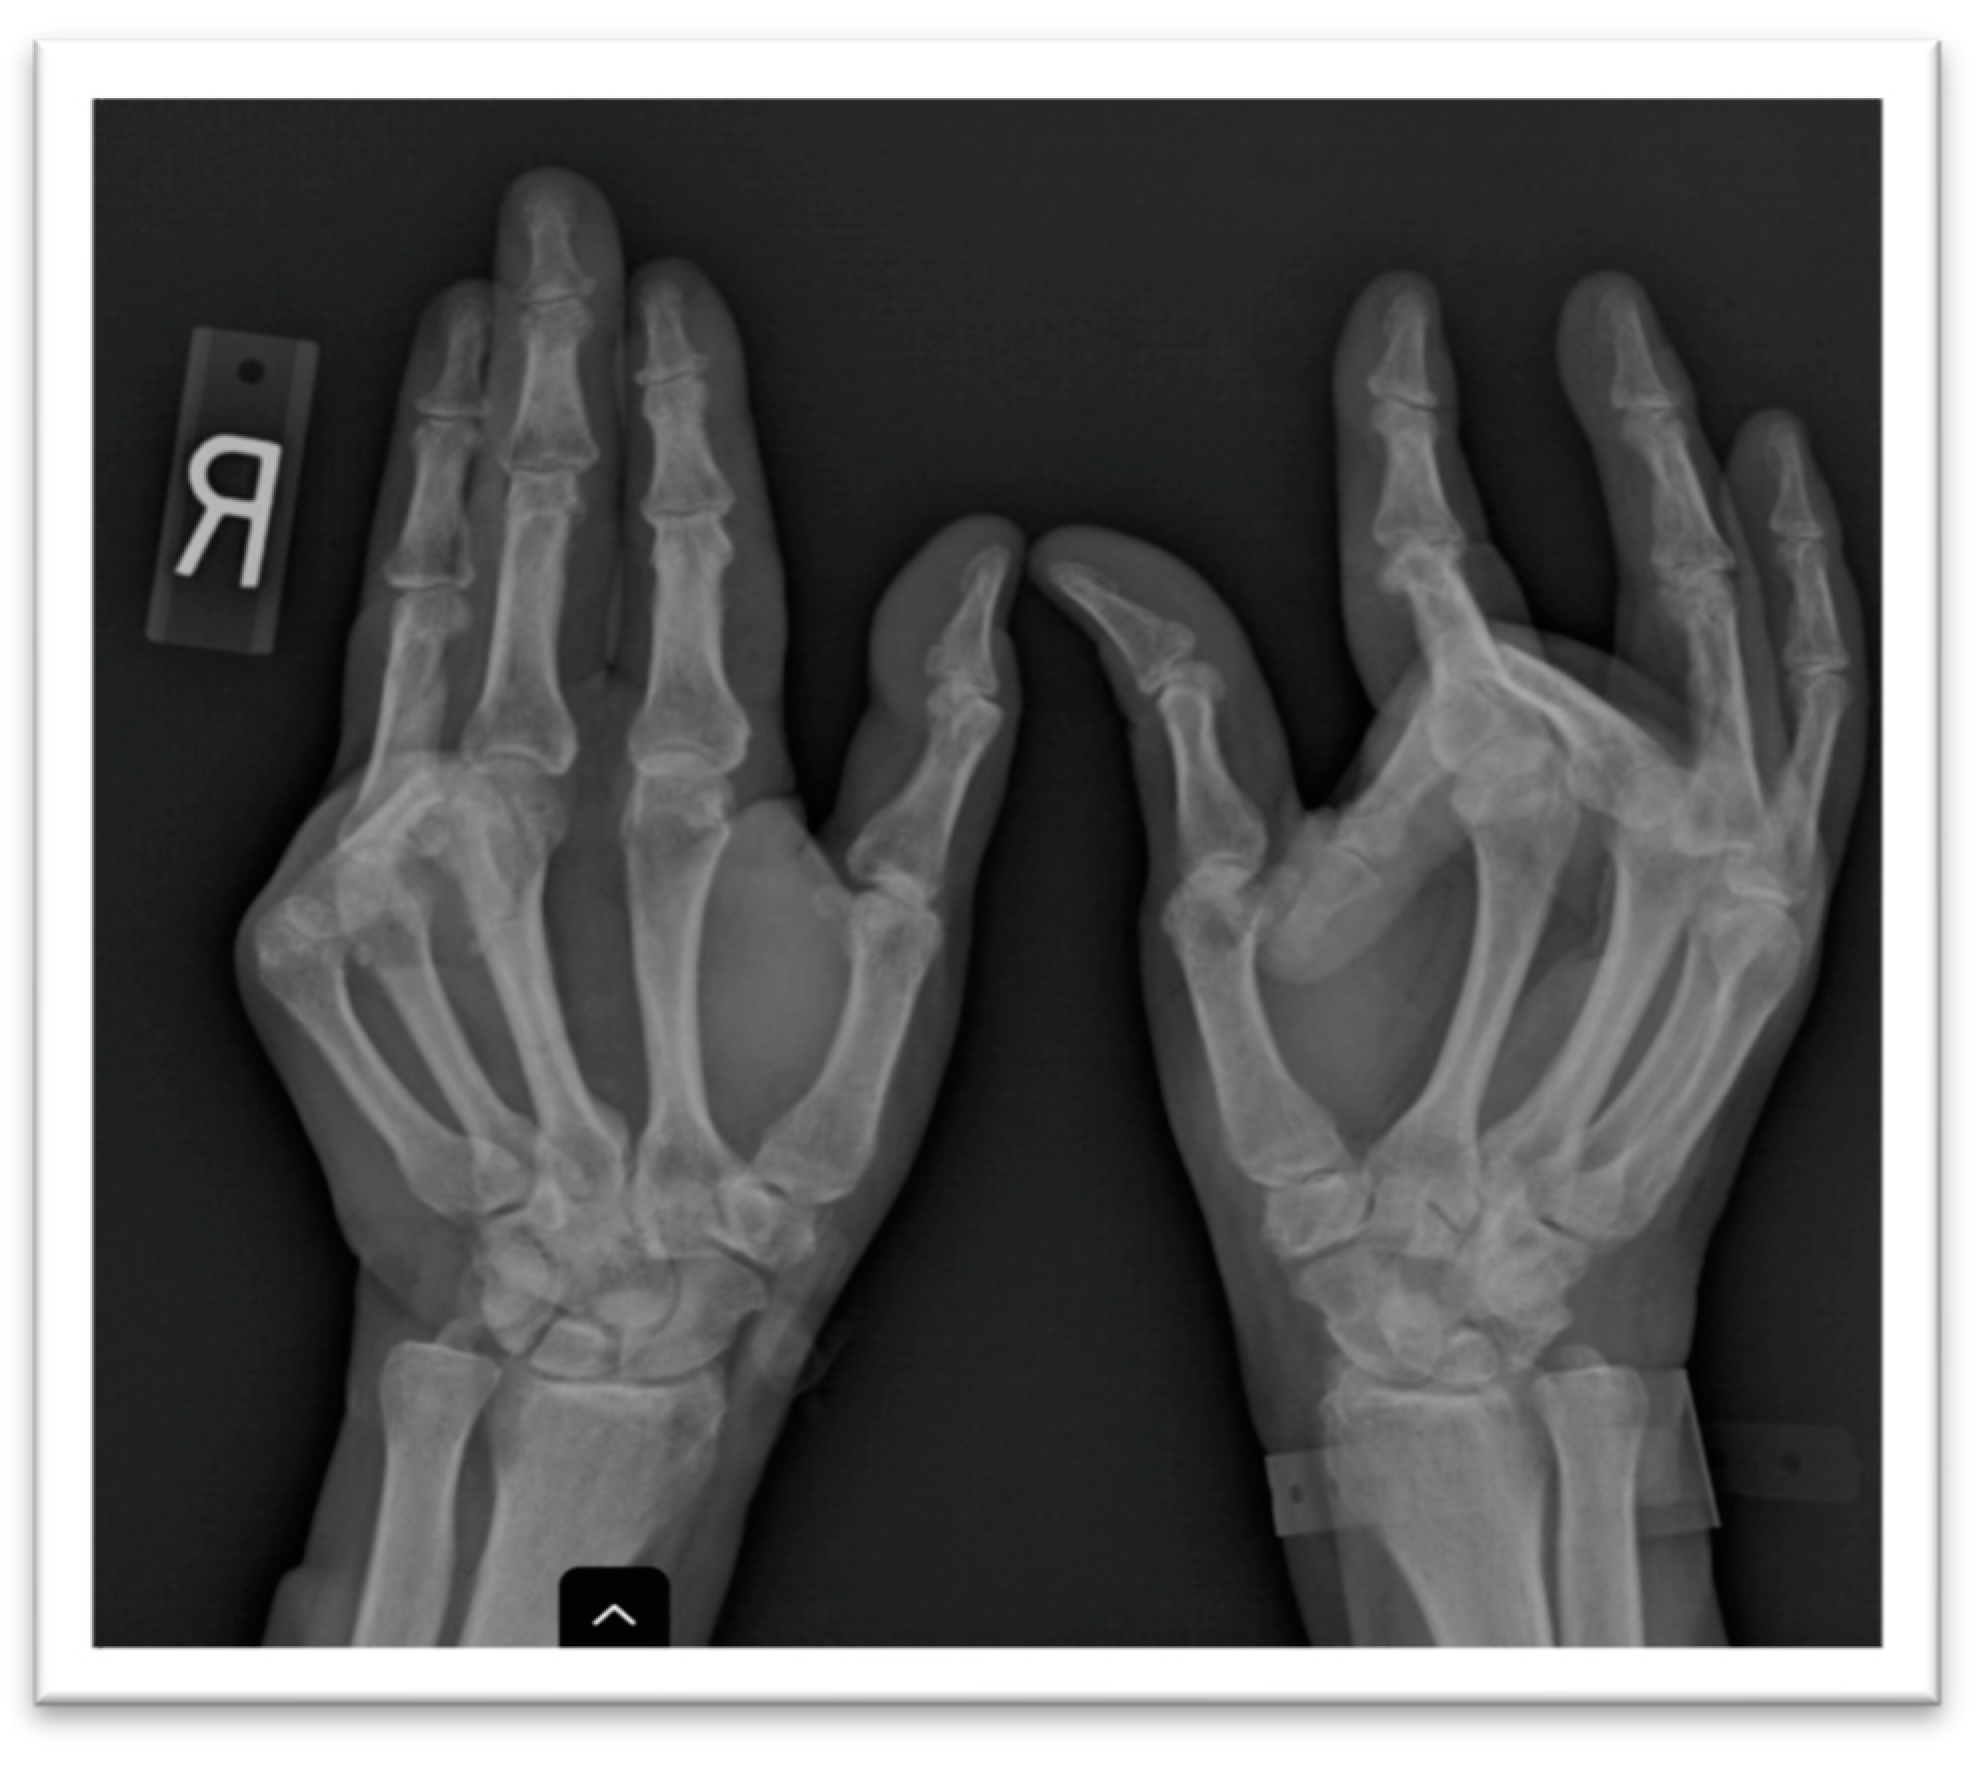

A plain X-ray of the hands showed juxta articular osteopenia, the large bony proliferation of the proximal interphalangeal joints, the erosion of this site in the fourth digit of the left hand, and the fixed flexion of two digits with subluxation (Figure 2). A hand ultrasound confirmed the presence of osteophytes defined by a step-up type of lesion, one large erosion in the right hand and signs of calcium pyrophosphate dehydrate deposition. A foot ultrasound indicated the presence of the double-contour sign at the first metatarsal, compatible with the patient’s previous diagnosis of gout. The hand joint lesions were indicative of destructive osteoarthritis (OA) but with atypical distribution; thus, more tests were deemed necessary to confirm the diagnosis and etiology.

Since the patient’s joint complaints were persistent despite usual analgesia, a plain X-ray was performed showing large bony productions of the second and fourth left proximal interphalangeal joint, an erosion of the right metacarpal bone, multiple subluxations, subchondral sclerosis and the fixed flexion of two of the digits, corresponding to a clinical bilateral Dupuytren’s contracture.

Figure 2. Plain X-ray of hands showing prominent interphalangeal bony productions and subluxations of multiple digits.